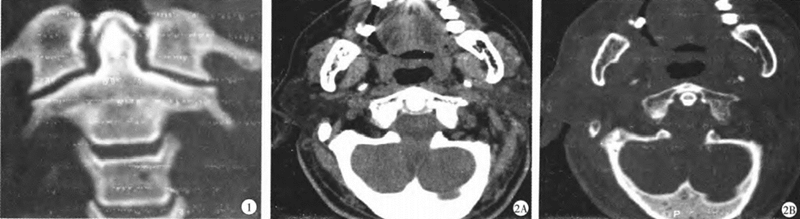

1.颈椎CT冠状面重建显示:齿状突周围韧带钙化,“晕圈样征象”2.颈椎CT横断面显示齿状突后方韧带钙化(A软组织窗;B骨窗)